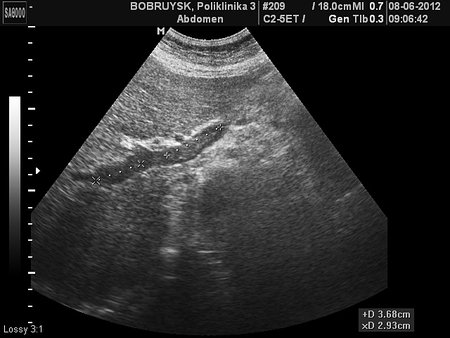

Женщина 62 лет.

Наблюдалась и лечилась в Минске, заключение подтверждено ангиографией там же.

- Тромбоз правой и левой ветвей воротной вены